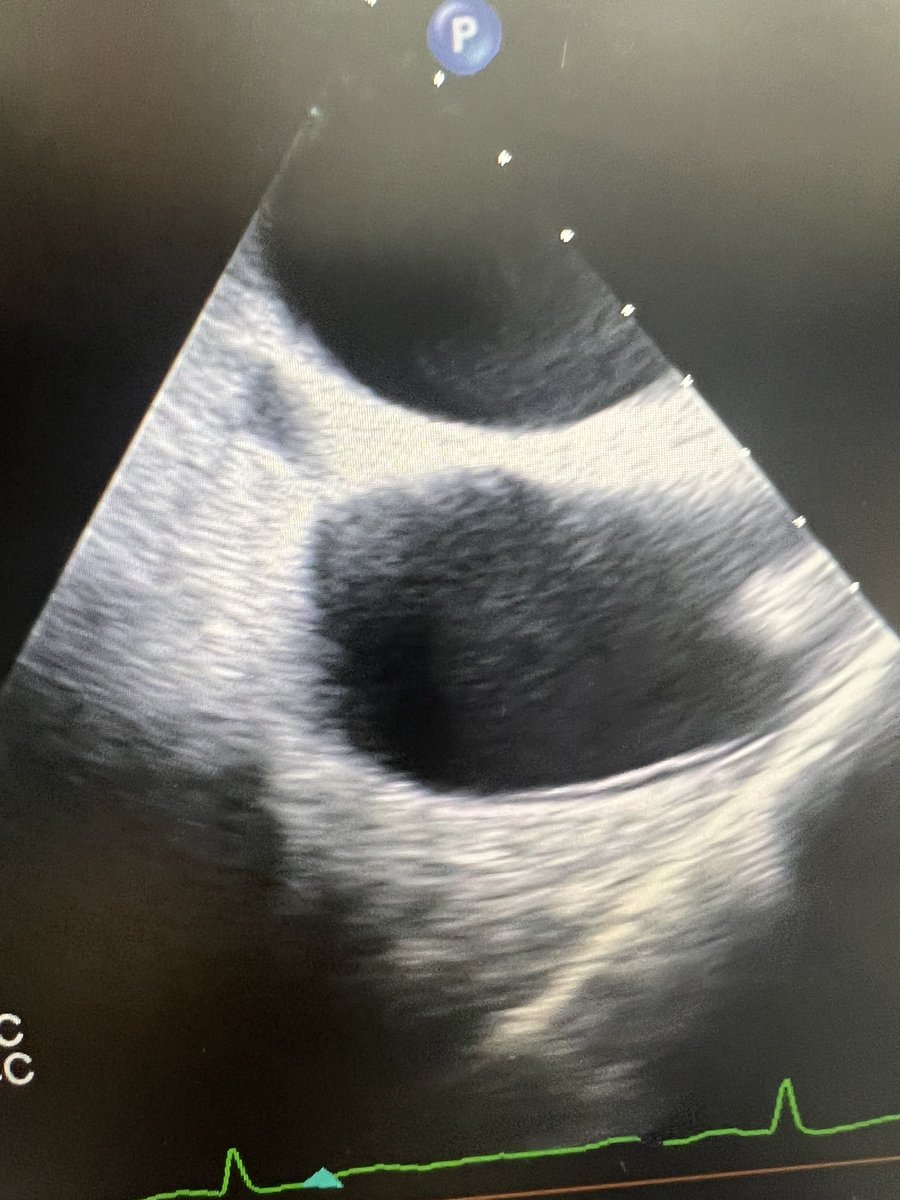

Proud to launch our official ECMO program at @mercy_health St Vincent Medical Center, Toledo. A step toward enhancing ability to care for sickest patients in community with life threatening cardio-pulmonary illnesses. Thanks to entire leadership and steering committee. @tcctoledo